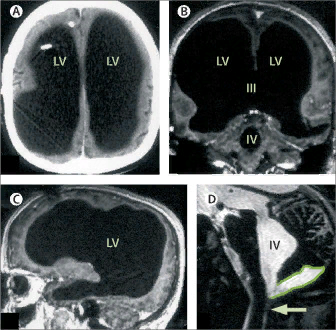

Спустя 30 лет мужчина обратился к врачу с жалобой на лёгкую слабость в левой ноге. Каково же было удивление врача, когда он увидел, что череп пациента на 90% заполнен жидкостью. Первое заключение гласило, что внутренняя часть мозга практически полностью разрушена и остался лишь тонкий внешний слой функциональной мозговой ткани.

Тёмные области — заполненные жидкостью участки. Feuillet et al./The Lancet.

Специалисты считают, что, благодаря специфическому течению болезни этого человека, когда жидкость в мозге накапливалась в течение десятков лет, у его мозга было достаточно времени, чтобы перестроиться. В результате, у мужчины повреждено далеко не 90% головного мозга. Вероятнее всего, мозг уплотнялся в ходе течения болезни, и видимые 10% содержат гораздо бóльший, но плотно упакованный объём мозговой ткани.